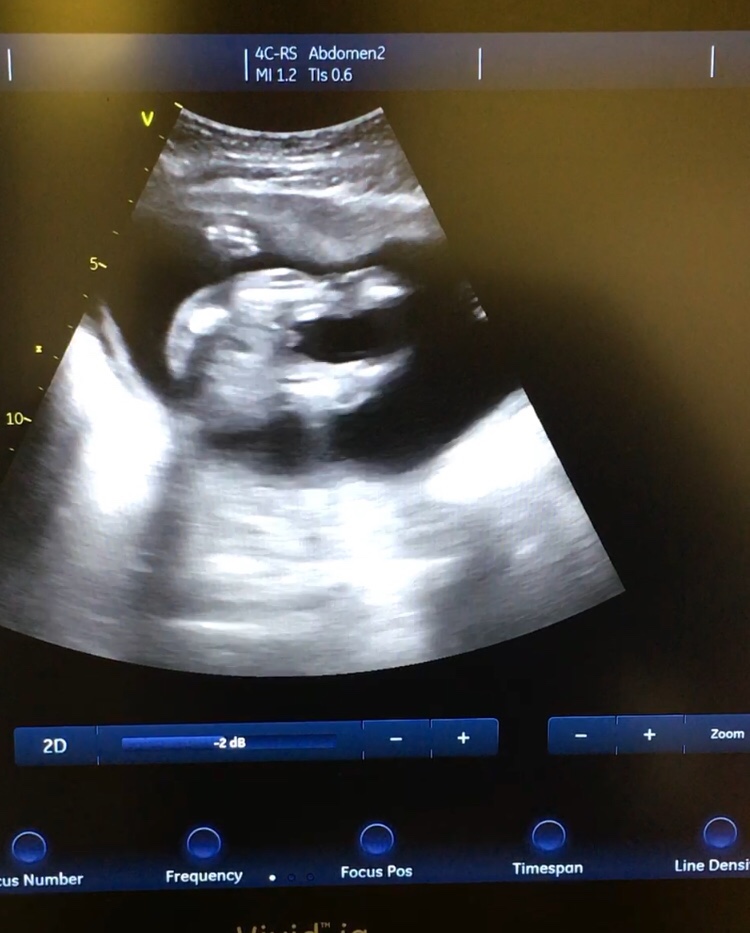

At 16 weeks we were told boy. Now at 18+4 we have been told possible swollen girl?? Is anyone able to shed any light? It won’t let me upload the video.Attachment 39493 I really want to go shopping xxAttachment 39492https://uploads.tapatalk-cdn.com/201...d91c74c9ac.jpghttps://uploads.tapatalk-cdn.com/201...118b00c07e.jpg